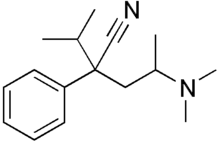

Others

- BDPC